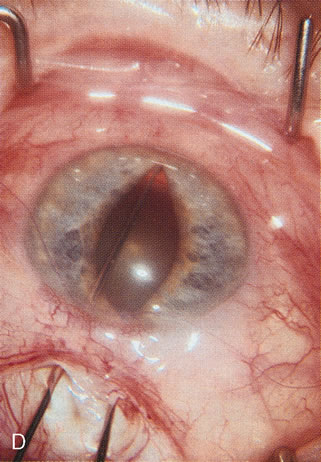

Fig. 3. Partial bleb failure following clear corneal phacoemulsification with foldable IOL. A. Preoperative bleb appearance prior to temporal lens extraction. Preoperative IOP was 12 mm Hg on no antiglaucoma medications. Time from 5-FU trabeculectomy surgery to lens extraction was one year. B. Bleb appearance 2 months after clear corneal cataract surgery with topical anesthesia. Following lens extraction, increased vascularity was noted along with decreased size of the filtering bleb. IOP increased to 20 mm Hg as early as 2 weeks after surgery, necessitating topical antiglaucoma therapy. C. High magnification view of bleb before lens extraction demonstrates diffuse pale bleb. D. High magnification view of bleb 2 months after surgery. There are vessels surrounding the nasal side of the bleb and the overall bleb size is smaller.